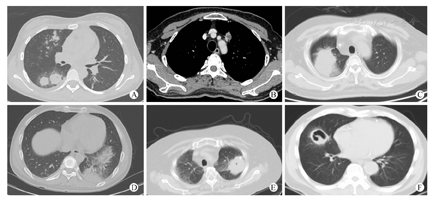

曲霉菌感染最常见的影像表现是多发大结节(图1),占75.8%,伴或不伴晕征(图2A),伴或不伴内部低密度及空洞(图2B),部分可见空气半月征。其他表现依次为实变(图2C、图2D)、肿块(图2E、图2F)、小结节及树芽征,大结节、实变及肿块可单独出现,小结节及树芽征多为伴随表现。出现胸腔积液的比例差异无统计学意义。

对几种主要病变的征象细节进行分析可以发现,以大结节为主要表现者,晕征、反晕征或病变内低密度、含气支气管征、空洞在两种感染中差异无统计学意义(P>0.05),体现空洞特点的内壁光滑与否,两种感染间差异无统计学意义(P>0.05)。表现为实变者,含气支气管征在细菌感染病例多见(P<0.05),空洞在曲霉菌感染多见(P<0.05),晕征、反晕征和病变内低密度影、胸膜下楔形实变两者比例差异无统计学意义(P>0.05)。表现为肿块者,曲霉菌感染病变多为单发(P<0.05),内容易看到空洞、空气新月征,但空洞内壁的光滑与否两者无区别(P>0.05)。晕征、含气支气管征、反晕征及病变内低密度的比例差异无统计学意义(P>0.05)。

肺曲霉菌感染根据感染者免疫状态分别有非侵袭性、半侵袭性和侵袭性三种形式[7]。SOT后肺曲霉菌感染多属于侵袭性感染,根据侵袭的主要结构又分为两种:血管侵袭性和气道侵袭性。前者指真菌菌丝侵犯肺血管后引起栓塞、肺梗死和出血,影像表现为斑片样的气腔阴影、区域性的实变和模糊的结节浸润[8]。气道侵袭真菌感染相对少见,可引起上呼吸道或下呼吸道感染。真菌菌丝侵犯呼吸道基底膜,可在腔内形成由坏死组织、纤维素条带和菌丝缠绕形成的假膜进而阻塞气道,亦可形成气道壁的结节样增厚。对应的CT表现为气管支气管壁增厚、多发小叶中心结节、树芽征、实变。

空气半月征是肺曲霉菌感染的另一重要征象,常出现在第2周或以后,此时受者的免疫反应逐渐恢复[7]。此征象出现的概率差异也很大[9],也不是曲霉菌感染的特异征象,可见于细菌感染、肿瘤、血管炎、肺间质疾病甚至外伤。本组受者表现为肿块者较多,多为单发,内出现空洞及空气半月征的比例比细菌感染组高,应该与受者选择有关,部分受者CT检查时间较晚,病变发展增大,实变形成肿块样外观,内出现空洞的比例增高。细菌感染组空气半月征出现比例低,可能因为检查时间较晚,坏死较多,已形成空洞而不是典型的空气半月征。